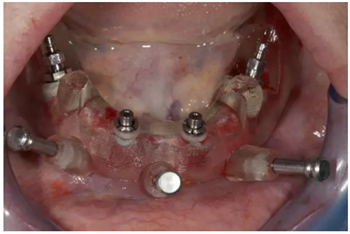

后期修復(fù)

手術(shù)后90天拍攝連帶內(nèi)錐形連接愈合基臺(tái)的X光片。

試戴上頜NobelProcera CAD/CAM海德式桿卡(IBO)以及下頜NobelProcera二氧化鋯種植橋(PIB)。

手術(shù)后16周最終修復(fù):上頜覆蓋義齒是卡扣在鈦桿卡(IBO)上,義齒牙冠部分是由二矽酸鋰玻璃陶瓷制作的單冠。下頜的氧化鋯種植長橋(PIB)上同樣也制作二矽酸鋰玻璃陶瓷的單冠并進(jìn)行粘接。

手術(shù)后16周最終修復(fù)X光片:計(jì)算機(jī)輔助導(dǎo)板引導(dǎo)種植能夠保證在All-on-4治療中精準(zhǔn)安全地植入軸向和傾斜植體。